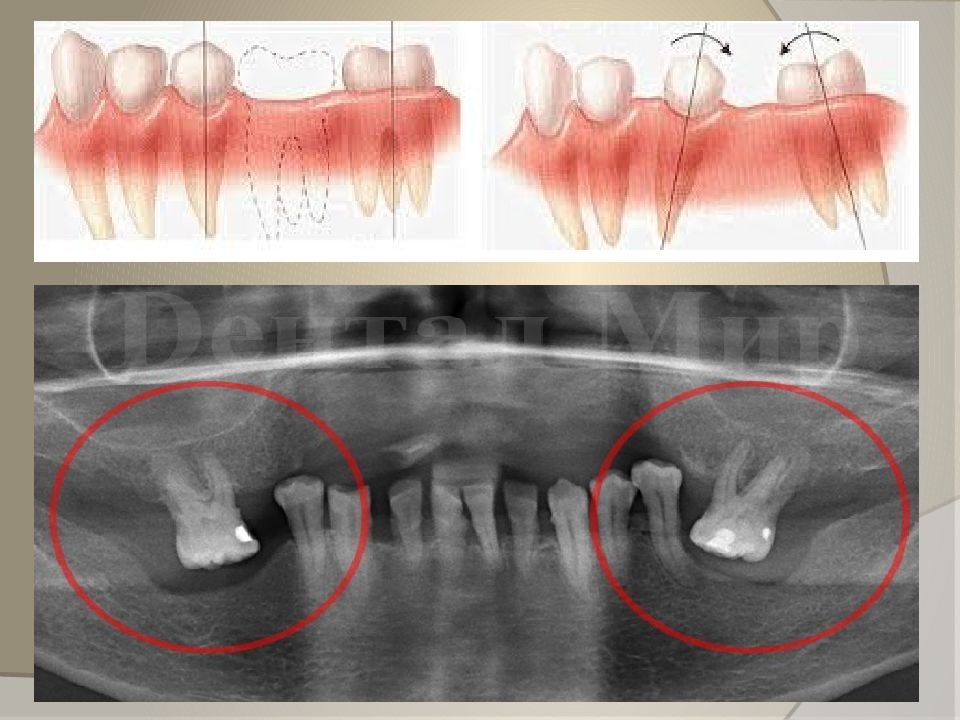

Симптоматика основных поражений зубных рядов 4. Вторичные деформации (перемещения) зубов: Конвергенция – наклон зубов в сторону дефекта; Дивергенция – наклон зубов в сторону, противоположному дефекты; Наклон в вестибуло - оральную сторону; Феномен Попова – Годона ; Ротация; Комбинированные перемещения.

Изображение слайда